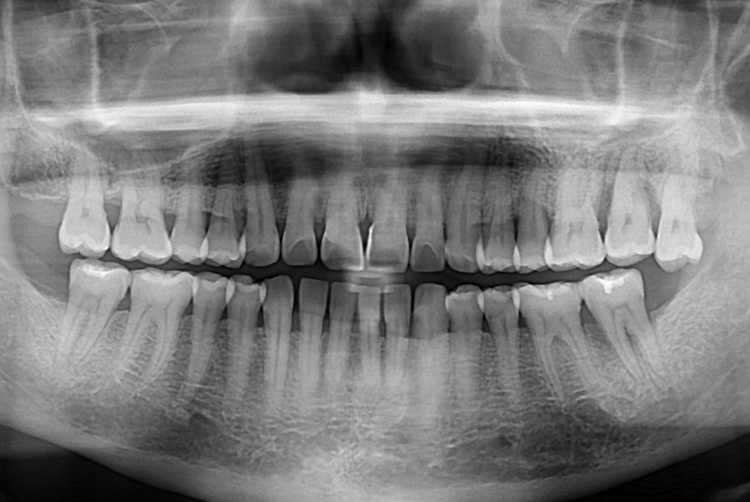

[임플란트] 어금니 임플란트

치료전 : 2017-11-28